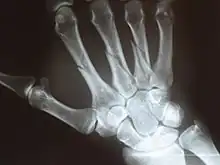

X-ray

X-ray image of right hand with thumb on left.

Multiple fractures of the metacarpals (aka broken hand). (Right hand shown with thumb on left.)

X-ray image of human infant left hand.